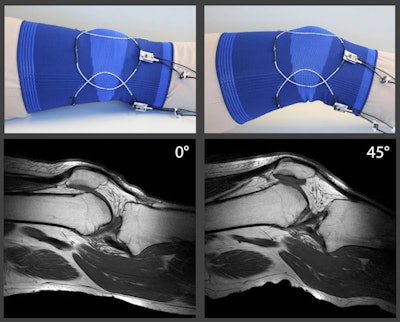

To adapt this technology for clinical application, the researchers combined several stretchable elements into a wearable coil array. In the first iteration, the coil array was attached to stretchable textile material. They then added a stretchable material to create an outer layer, or casing, into which the coil element was inserted.

To test the technology, the researchers tried their stretchable MRI coil on a 3-tesla MRI scanner (Ingenia, Philips Healthcare). At various angles, the resultant MR images showed the interaction of the knee, thigh bone, and cruciate ligaments and how they interact as the knee flexes. The researchers also performed a dynamic knee study, during which a volunteer moved his knee freely inside of the scanner. Again, the exercise was successful in showing how knee movements affect the cruciate ligaments.